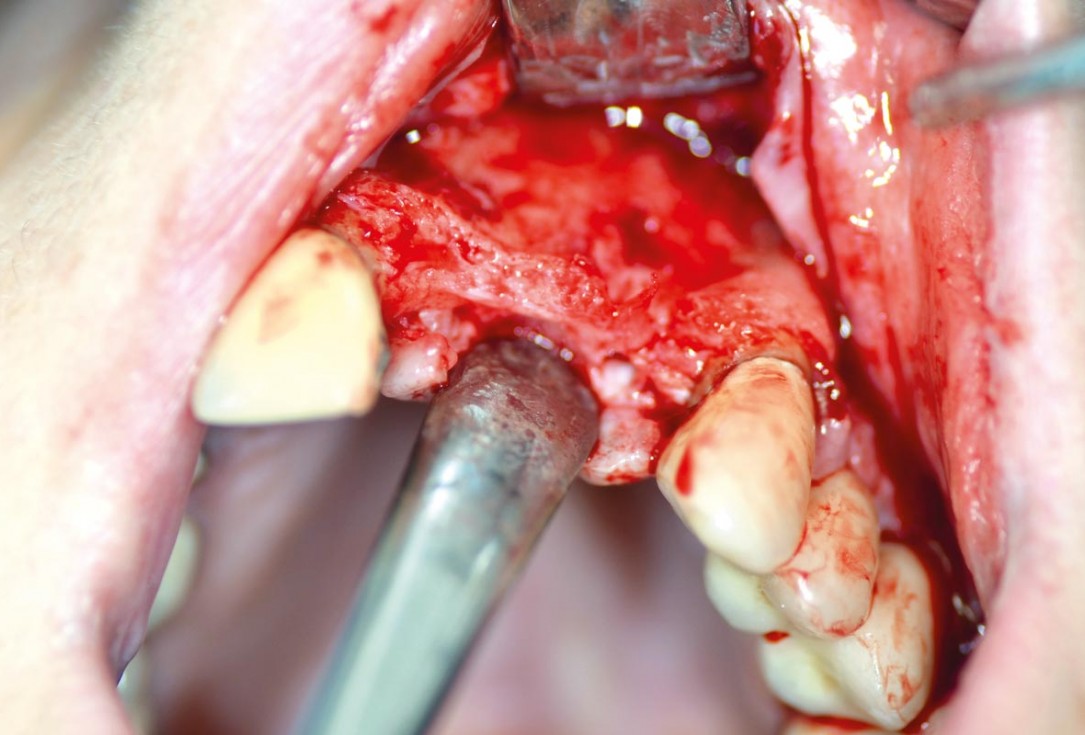

Initial clinical situation with gum recession and labial bone loss eight weeks following tooth extraction